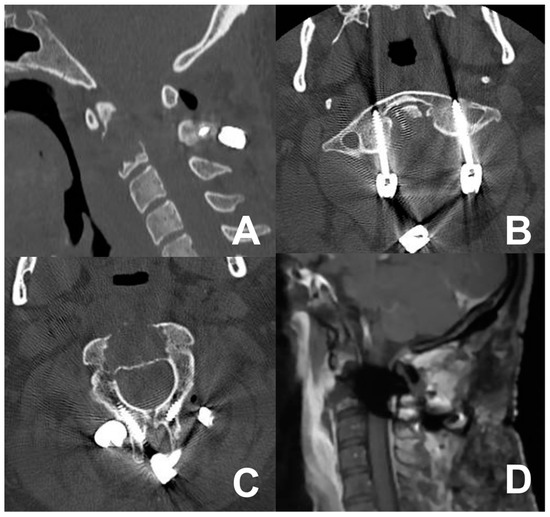

3.4. Third Case: Two-Staged Transoral Approach and Posterior Midline Occipitocervical Fusion—Subtemporal/Infratemporal and Retrosigmoid Approaches for Tumor Relapse